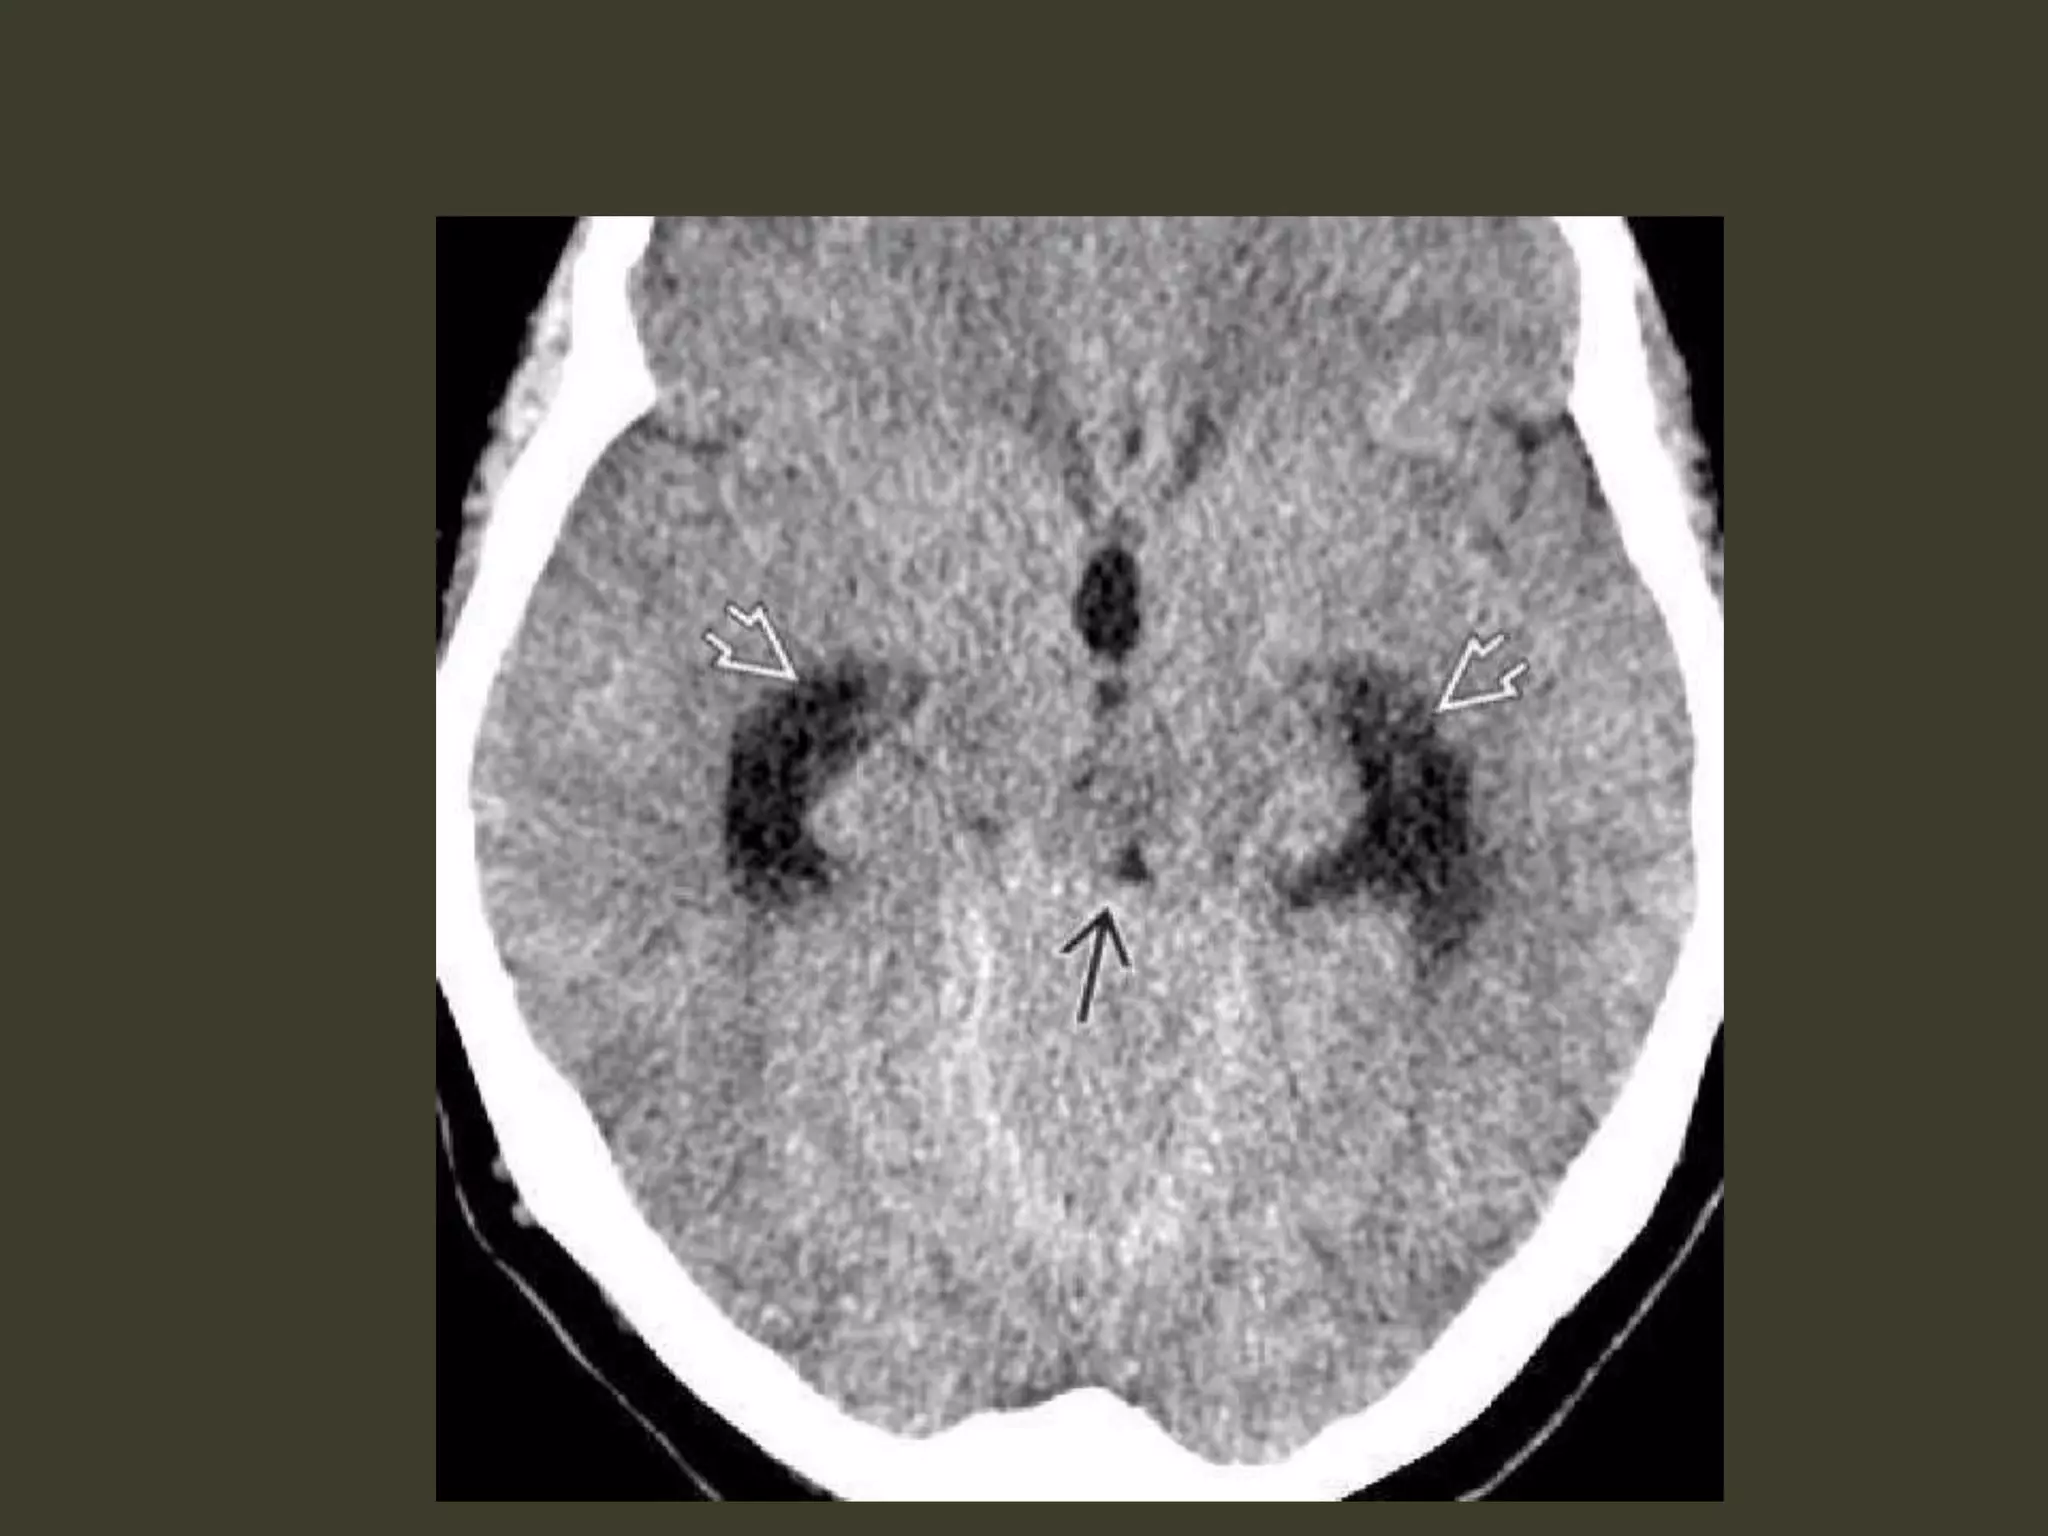

bilateral DTH both hemispheresbecome swollen the whole central brain is flattened against the skull base All the basal cisterns are obliterated hypothalamus and optic chiasm are crushed against the sella turcica

Complete bilateral DTH bothtemporal lobes herniate medially into the tentorial hiatus midbrain and pons displaced inferiorly through the tentorial incisura The angle between the midbrain and pons is progressively reduced from 90° to almost 0°

Duret hemorrhage "Top-down" masseffect displaces the midbrain inferiorly closes the midbrain-pontine angle Perforating arteries from basilar artery are compressed and buckled

hypothalamic and basal gangliainfarcts complete bilateral DTH perforating arteries from the circle of Willis compression against the central skull base hypothalamic and basal ganglia infarcts